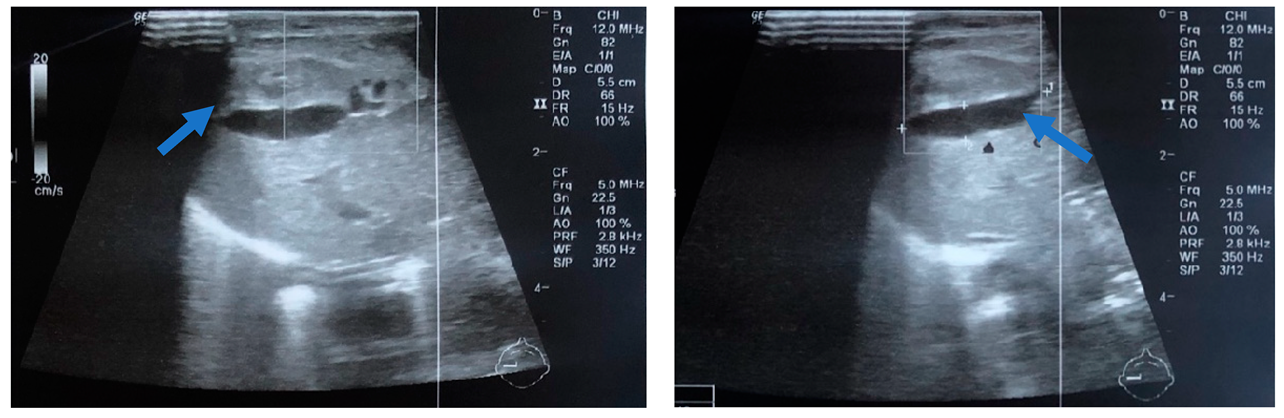

In order to differentiate the possible causes of the hypovolemic shock, the neonate had a transfontanellar brain ultrasound, which was negative for bleeding. The abdominal ultrasound revealed a cystic formation of 2.1 cm × 0.5 cm in the anterior portion of the right liver, inhomogeneous liver, and intra-abdominal fluid collection (Figure 2). Radiography of the chest and abdomen revealed abdominal distension (Figure 3). The NICU team and the pediatric surgical team, suspected a possible hemorrhage in the peritoneal cavity due to diffuse liver injury and SHL.

Figure 2.

Abdominal ultrasonography depicting a cystic formation 2.1 cm × 0.5 cm in the anterior portion of the right liver, with anechoic characteristics (blue arrow).